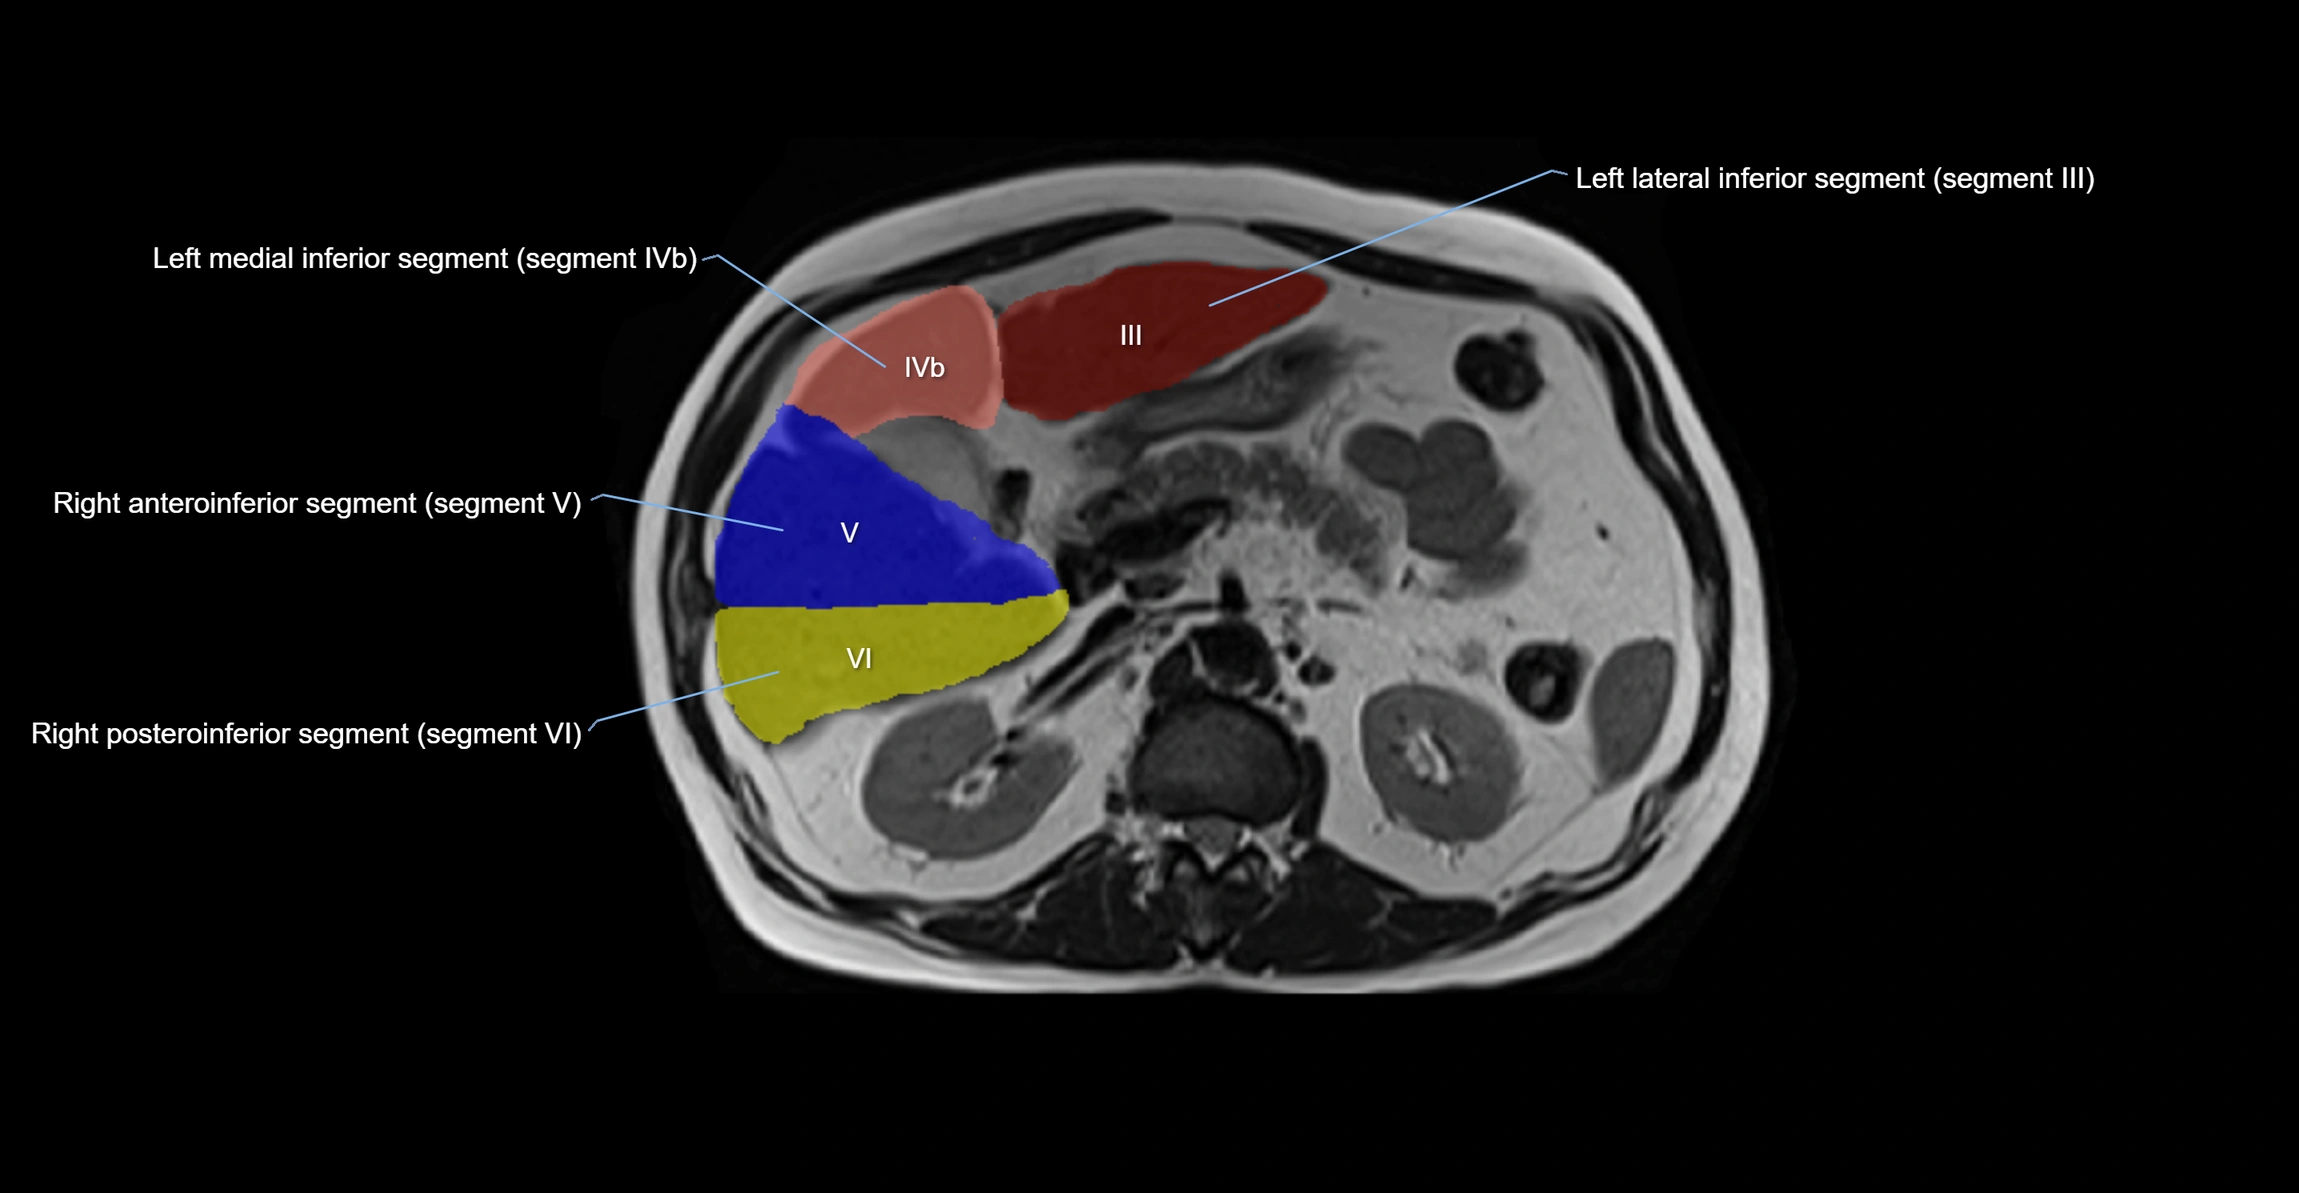

MRI image

image